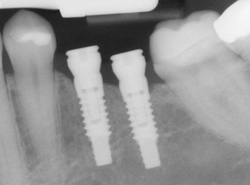

Dental implants are small titanium rods surgically implanted into your jawbone to replace missing teeth. As you heal from the surgery, the rods fuse to your bone and form a strong and sturdy root, which looks and feels like a natural tooth. When the implant is ready to be restored with a crown or bridge, it will feel natural to bite, chew and speak. The power behind dental implants is that they help to prevent bone loss in your jaw. If you have lost a tooth, the bone beneath it will slowly begin to shrink through the process of resorption. This can cause your face to appear sunken in, cause the lips to look thinner and more wrinkled, cause your cheeks to have a more hollow appearance, and make it very difficult to have replacement teeth placed in the future. However, when you have an implant placed in your jaw at Ash & Rowan Family Dentistry, it helps prevent bone loss by replacing the tooth roots that your natural teeth had before.